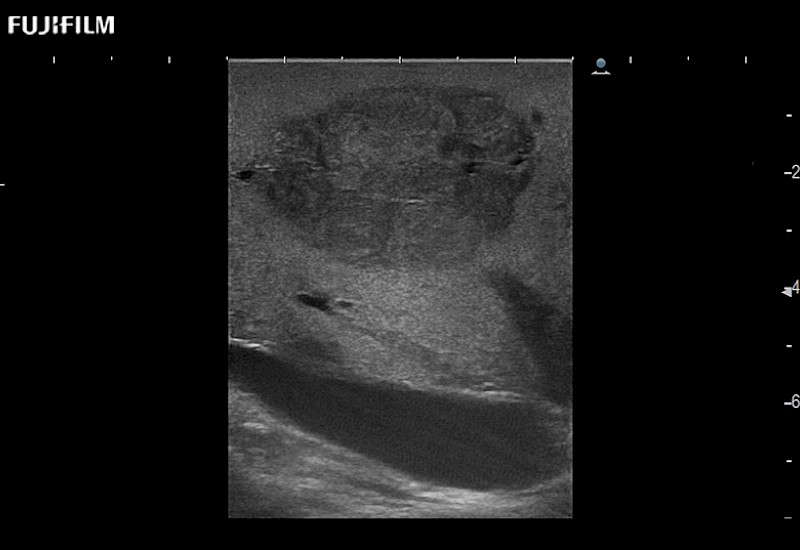

Curved array deep penetration “T” style finger-grip transducer for open surgical procedures.

Main Specifications:

Curved array “T” style finger-grip transducer for open surgical procedures.

Curved array deep penetration “I” style finger-grip transducer for open surgical procedures.